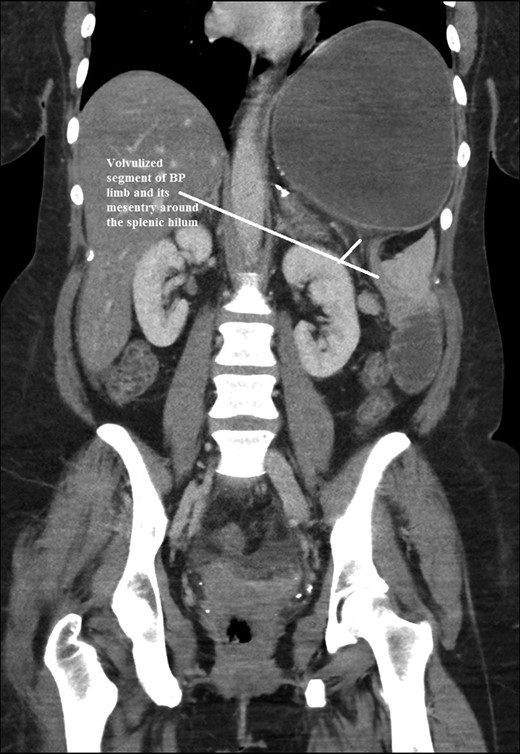

The intraoperative findings were not consistent with the radiological findings (Figs 1–4). As shown in the CT scan of abdomen and pelvis; multiple loops of dilated small bowel were seen, more predominantly dilated and matted bowel complex just above the spleen. The dilated bowel complex was decompressed using needle aspiration to help reduction of the bowel loops. The ileo cecal junction was then identified and traced back to the perisplenic hilar region. The trifurcation of three bowel loops (Roux limb, biliopancreatic limb and common limb) were identified with identification of ligament of Treitz. The prior gastric bypass was of ante colic- ante gastric type and Peterson’s defect was not closed. The above described bowel trifurcation had sunken postero- inferior to the spleen and had herniated through a potential space underneath the spleen and torsed around the splenic vessels and hilum. This picture was consistent with perisplenic small bowel volvulus. As noted earlier there was a massively dilated proximal small bowel segment above the spleen, displacing it caudally. Careful adhesiolysis was performed inferior to the spleen to release the segment of the trifurcation. The bowel segments once reduced were assessed and appeared viable. Of note, the spleen appeared better perfused after reduction. The remnant hernia defect of size 2 × 3 × 2.5 cm around the hilar region was then approximated using interrupted non-absorbable sutures. Enterotomy at the decompression site was closed with non absorbable suture. All potential sites of IH were re-examined and there was no evidence of any other internal herniation. Coelomic cavity was thoroughly irrigated and operation concluded successfully. Postoperative hospital stay was uneventful, and the patient was discharged home after two days.

Coronal CT scan of abdomen and pelvis showing volvulized bilio- pancreatic and Roux limbs within the obstructed segments in the splenic hilar region.

Coronal CT scan of abdomen and pelvis showing Volvulized segment of bilio-pancreatic limb and its mesentery in the spleen hilum.

Coronal CT scan of abdomen and pelvis showing Dilated jejunal segment causing caudad splenic displacement.